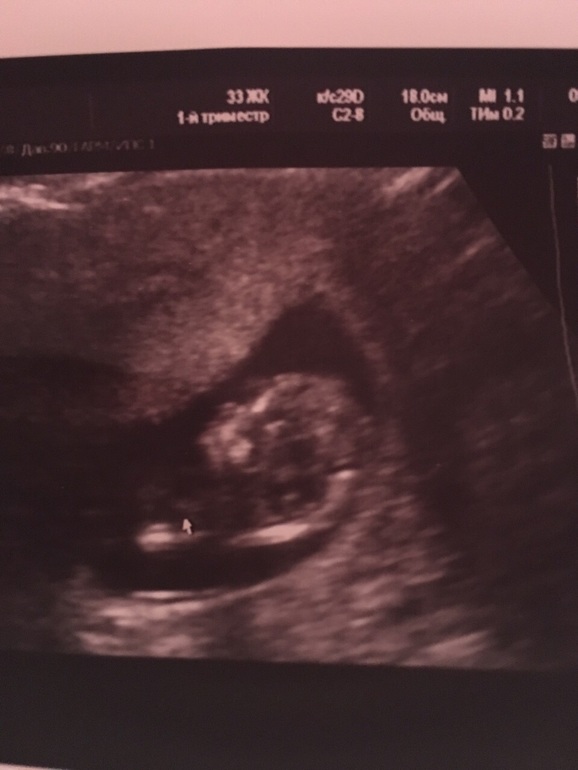

УЗИ в 11+3

Все у нас хорошо, по УЗИ опережаем на неделю:) замеры:ктр60мм

Сердцебиение 154/мин

ТВП1,4

Фотку с во весь" рост" не сделали , но Узистка сказала мальчик :)